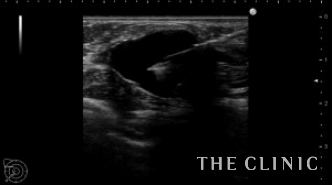

オイルシストは注射針で簡単に治療できますが、石灰化は摘出するしかありません。

今回は石灰化は治療せず、オイルシストのみ穿刺吸引しました。

吸引したオイルです。